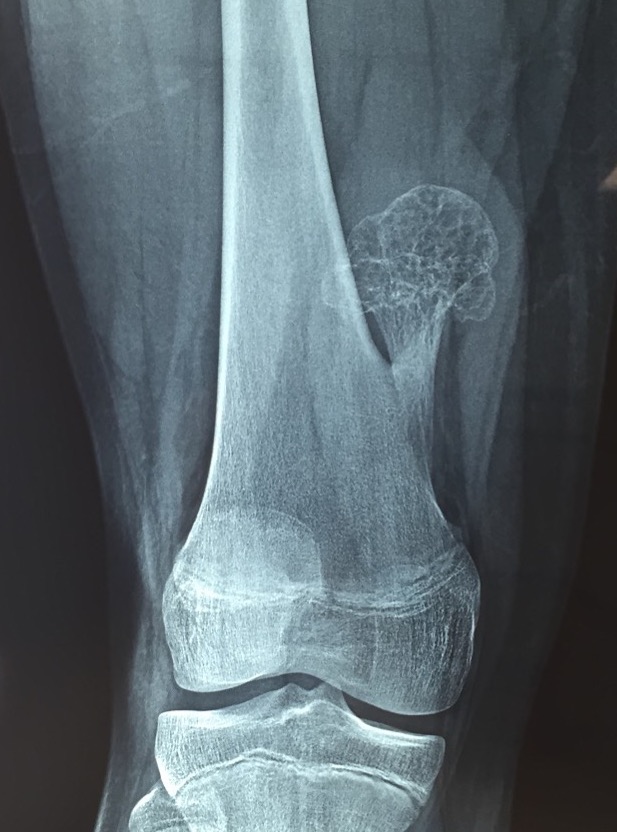

Definition

Cartilage capped bony projection on the external surface of bone

Types

1. Pedunculated - has a stalk, points away from joint

Pedunculated

Protuberant bony lesion arising adjacent to physis

- directed away from joint

- cortical bone and marrow space continuous

Proximal humerus

Bae et al J Pediatr Orthop 2014

- 31 patients with proximal humerus osteochondromas

- anterior / lateral / posterolateral debulked 92%

- posteromedial debulked 68%

- recurrence 2/31 (6.5%)